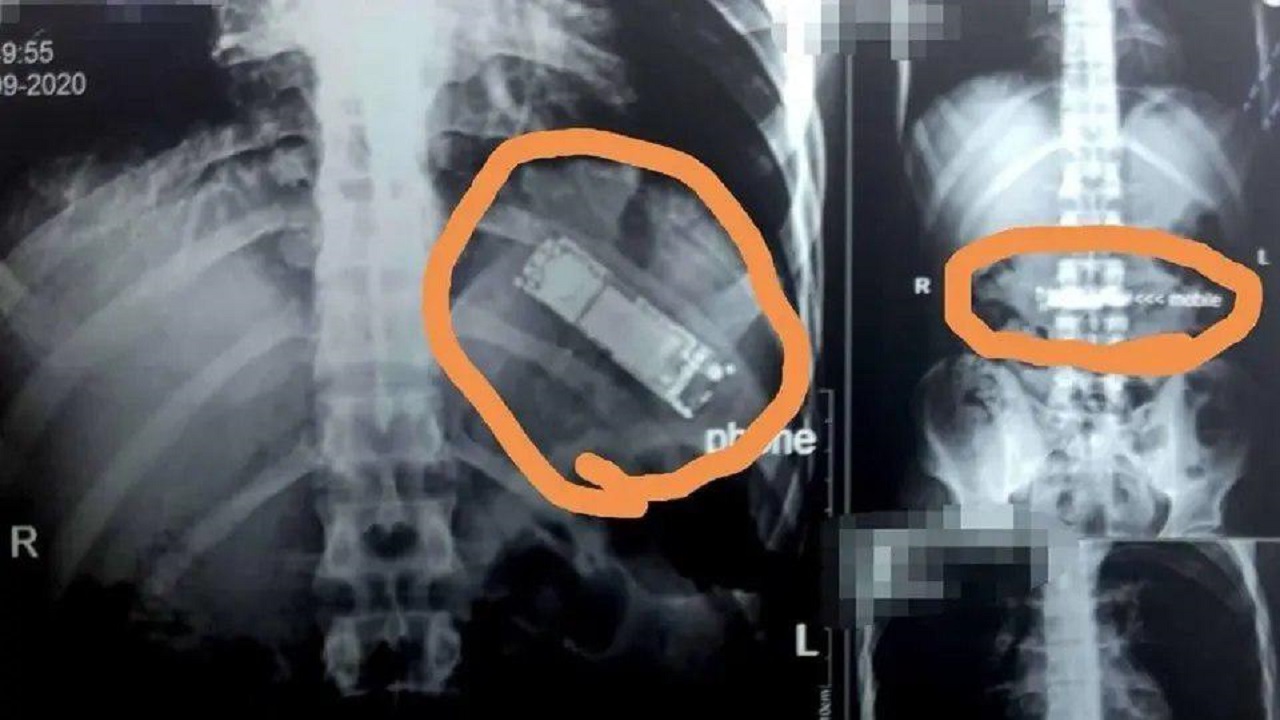

تیم پزشکی بر همین اساس تصمیم گرفت از معده او عکس‌برداری کند و نتایج این عکس‌ها حیرت‌آور بود. آن‌ها جسم مشکوکی در معده او یافتند که مشخص شد یک دستگاه تلفن همراه است.

این بیمار به پزشکان گفت که ۷ ماه پیش بعد از یک شوخی با دوستانش، این تلفن همراه را بلعیده و تصویر کرده که هر وقت بخواهد، می‌تواند از طریق استفراغ کردن، تلفن مذکور را بالا آورده و از بدنش خارج کند.

او هیچ چیزی در این باره به خانواده‌اش نگفته و همزمان همه تلاش‌هایش برای بالا آوردن تلفن همراه بلعیده شده راه به جایی نبرد. پزشکان بیمارستان دانشگاهی بن‌ها طی یک عمل جراحی فوری که دو ساعت به طول انجامید این تلفن را از معده حسن رشاد خارج کردند.

پزشکی که این عمل جراحی را انجام داد، گفت: سرنوشت با این بیمار مهربان بود، زیرا که باطری این تلفن همراه داخل بدن او متلاشی نشده و او را مسموم نکرده است. این باطری ممکن بود داخل معده این فرد منفجر یا متلاشی شود و جان بیمار جوان را بگیرد.